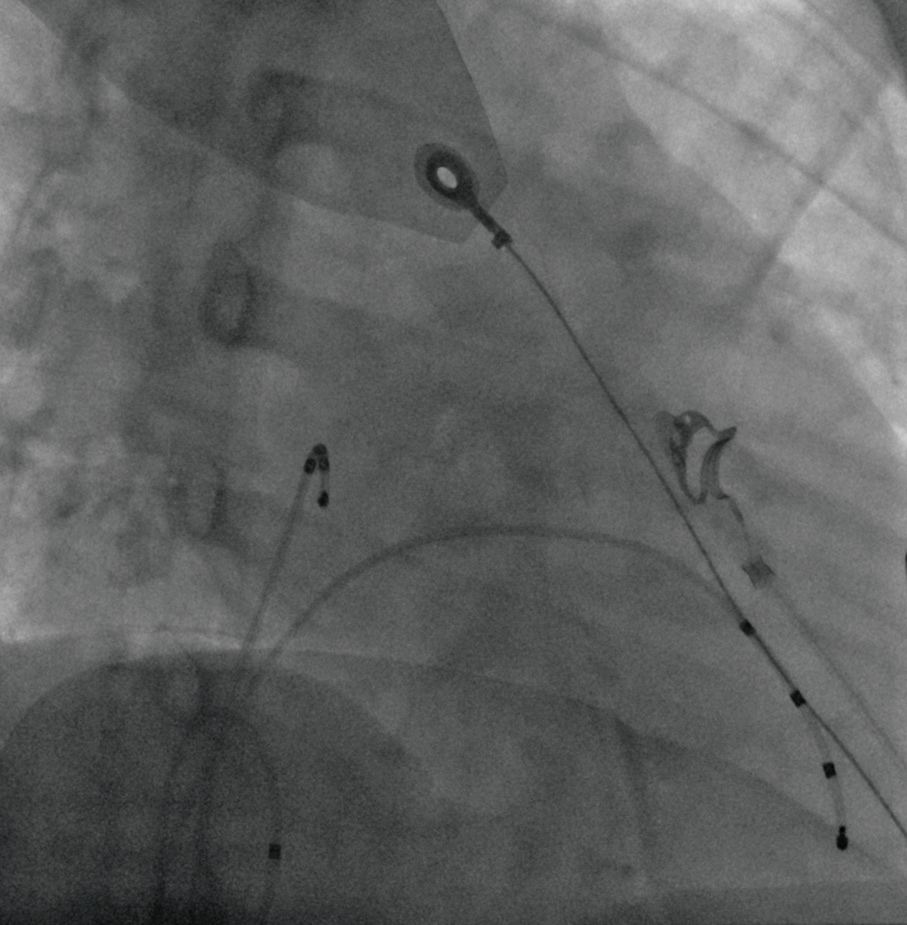

Система Artis Q.zen оснащена новой революционной технологией детекторов, основанной на кристаллическом кремнии, которая уменьшает электронный шум и позволяет получать изображения с ультранизкими уровнями доз. По сравнению с маленькими кардиологическими детекторами зона покрытия этих детекторов больше, что позволяет получить изображение сердца целиком.

Программное обеспечение CLEARstent Live  позволяет в режиме реального времени проверять положение стента при перемещении устройства, устраняя влияние движения сердца. Позволяет сократить время проведения процедуры и использовать меньше контрастного вещества.